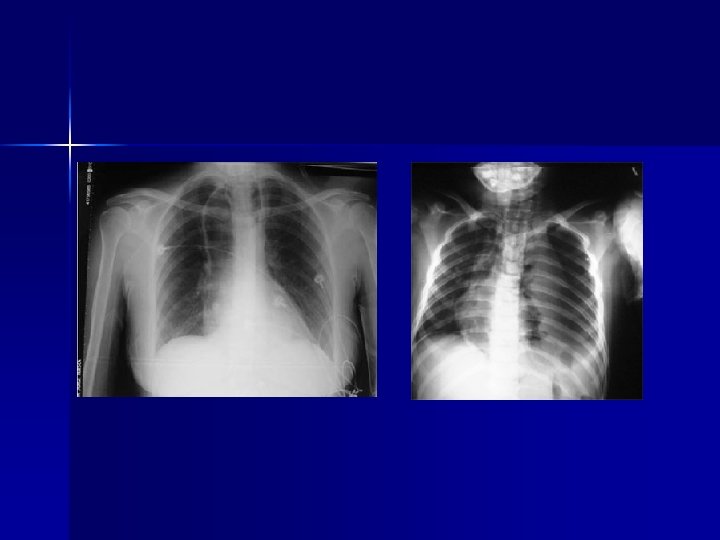

Rx TÓRAX Hemotórax: -Opacificación sello tórax -Sangrado de inicio > 1500 cc toracotomía -Sangrado es de 200 -300 cc/h toracotomía n Contusión pulmonar: -Patrón irregular intersticial -Disnea leve a Distress Respiratorio del Adulto -Magnitud puede no verse al inicio -Gases arteriales y Rx tórax seriadas (c/6 hrs) n